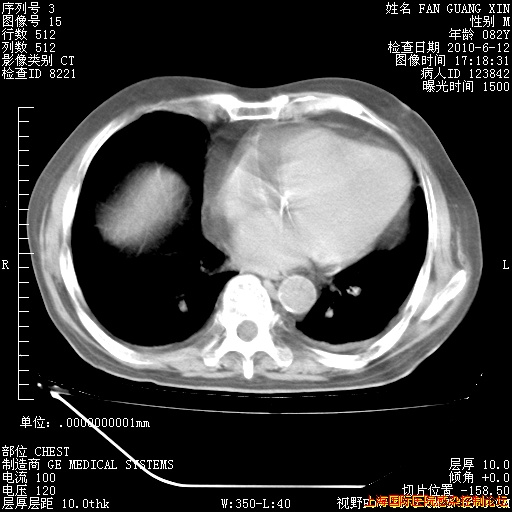

今天复查CT

今天CT

整整相隔30天的肺部CT好像有所好转啊。甲强龙减量第3天,需要观察体温。

海管,自昨日你和我通完话后,不知您岳父消化道症状有无缓解?体温怎样?阅读7.12日胸部ct,个人认为目前激素治疗是有效的,甲强龙减量是适宜的。因在抗痨治疗,需密切观察肝功、肾功能和血常规。不过,老年、长期住院和大量使用激素,很担心菌群失调发生